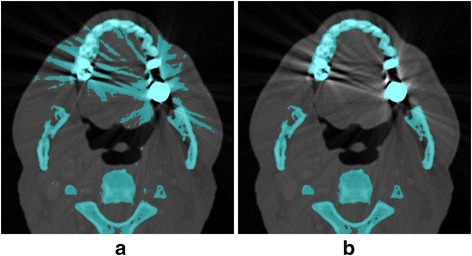

Novel imaging techniques should be adopted to assist the process of 3D printing to improve accuracy and efficiency. For example, both bone and iodine-enhanced vessels have high CT numbers and show up as bright structures in regular CT images. It can be challenging to separate such bones and vessels. Dual-energy CT, which uses the energy dependence of the x-ray attenuation coefficient, can easily differentiate these two materials [25]. In this case, a ‘bone removal’ process can be performed to remove bones while leaving iodine enhanced vessels. Thus, dual-energy CT acquisitions may be desirable for vascular models. Another challenge frequently encountered in 3D printing is image distortion caused from artifacts in patients who have metal implants. Metal artifacts substantially degrade the image quality of both CT and MRI, and contaminate surrounding anatomy. Novel metal artifact reduction techniques can be used to reduce metal artifacts, consequently improve the efficiency and accuracy of 3D printing (Fig. 3) [26].

Fig. 3.

CT images of a patient with dental fillings (a) and that after application of a metal artifact reduction algorithm (b). Pixels in blue color were results of thresholding segmentation, aiming to separate bone from soft tissues. Metal artifacts contaminated the segmentation in the original images (a) while was removed in the image with metal artifact reduction algorithm (b)